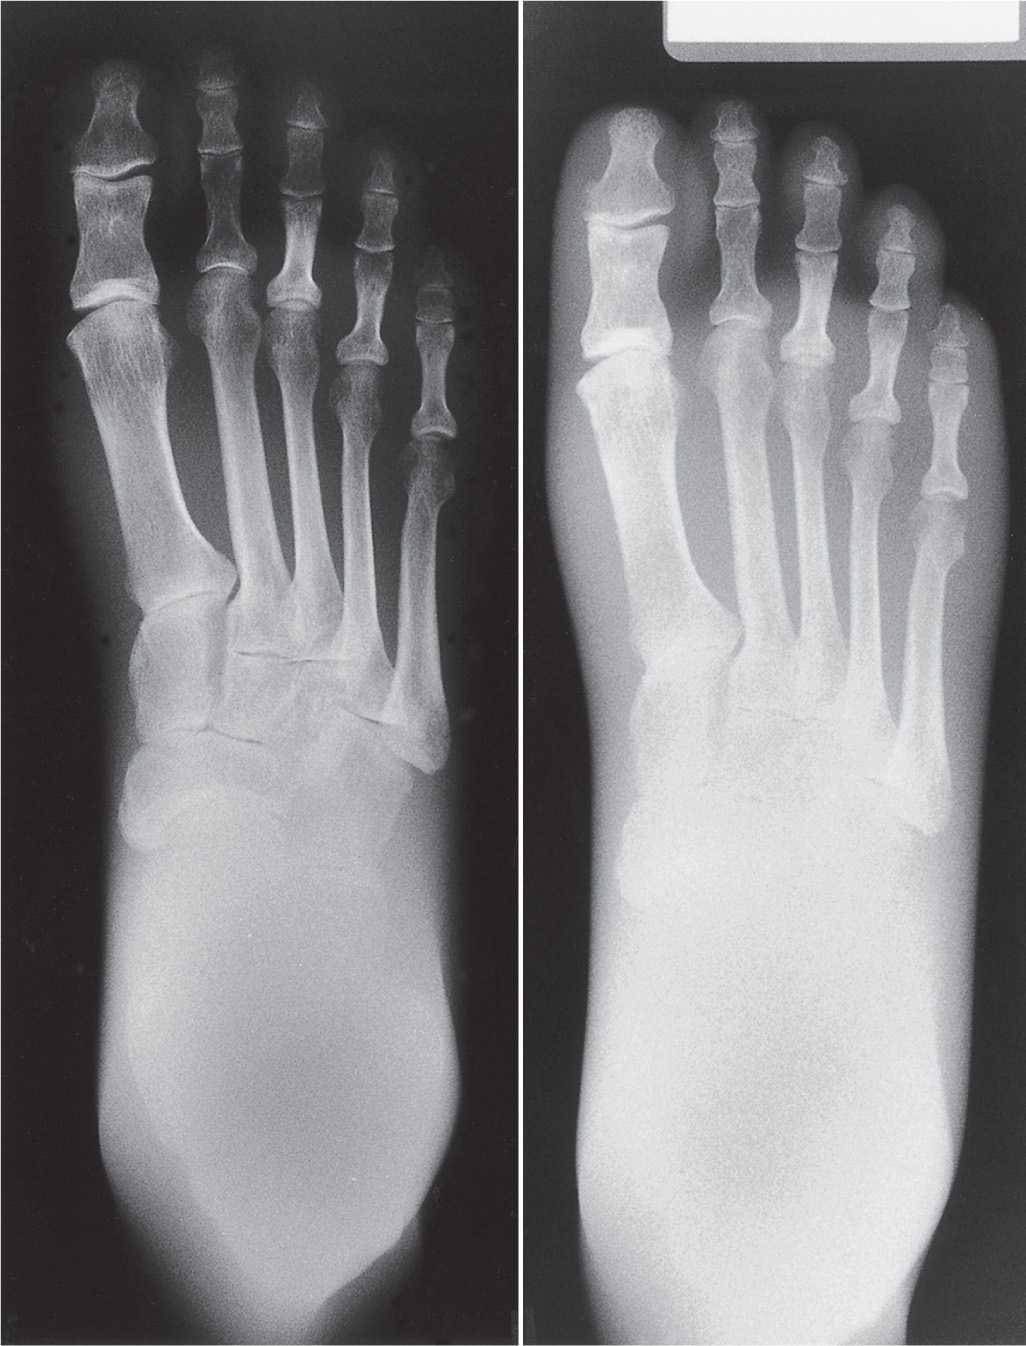

What Is Radiographic Density . learn how to identify and interpret the four main densities (bone, soft tissue, fat, and air) on conventional. It is measured by optical density, which. radiographic density (aka optical, photographic, or film density) is a measure of the degree of film darkening. Learn how kv, scatter radiation, and. the radiographic density is defined as the level of darkness in an x ray image, calculated by the radiation absorption by those tissues in that radiographic. The amount of darkness in the radiographic image reflects the radiographic density. radiological density is determined by both the density and the atomic number (the number of protons in an atom’s nucleus) of the material. radiographic contrast is the density difference between neighboring regions on a plain radiograph.